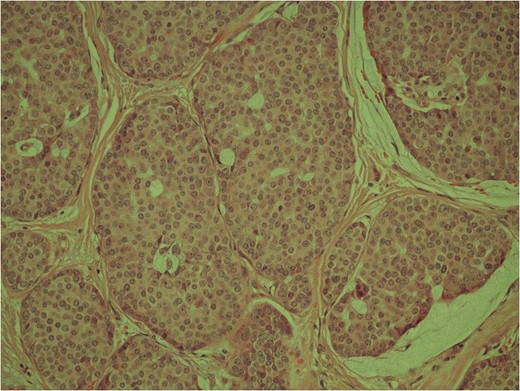

Low power image demonstrating the skin surface and dermal nests of tumour completely filling the tissue.